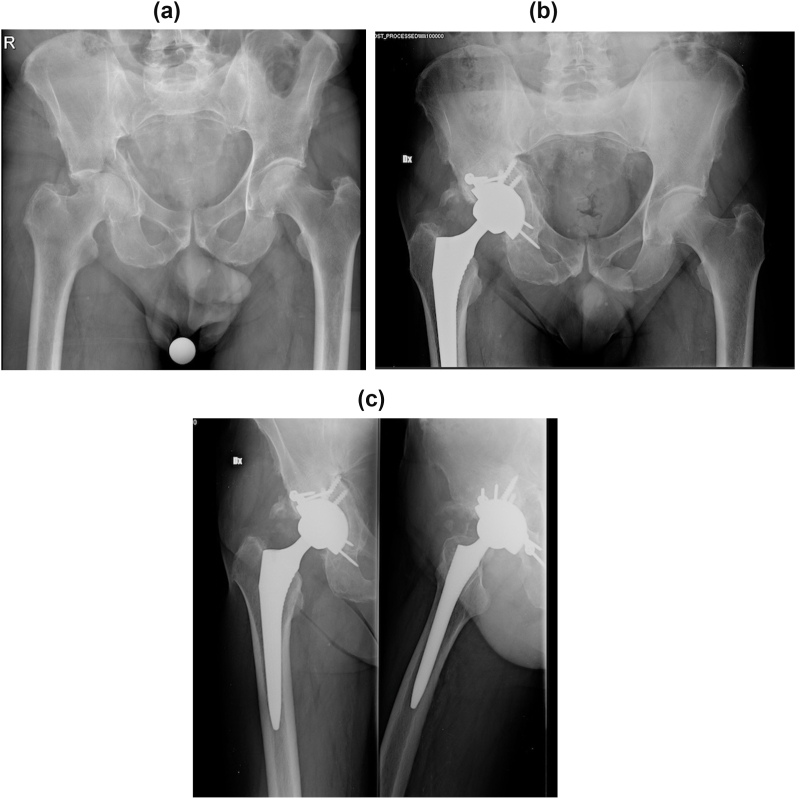

Fig. 2.

A. Preoperative xrays of an 82 years old male with T-shaped comminuted fracture B–C. Xrays at 2 years follow-up in anteroposterior and lateral views.

Comparison between fractures that involved only posterior wall and/or column (Fig. 1A–B) and fractures that involved also the anterior column (transverse, T-shape, isolated anterior column, posterior column + hemitransverse anterior column) (Fig. 2A–B) did not show statistically significant differences but surgical time. Surgical time may be longer in more complex fracture often due to the challenging reduction. On the other hand, we did not found differences in the outcomes between easier and more complex fractures.